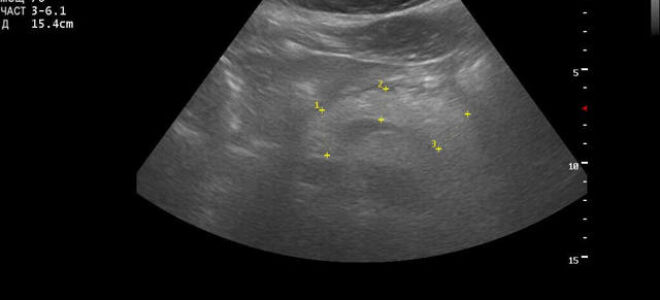

Узи поджелудочной железы: норма, расшифровка результатов, показателей

Заболевания поджелудочной железы имеют схожую симптоматическую картину.